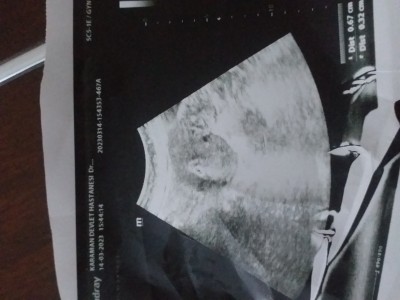

Selam  canim  birsey  sorcam  benkm  hcg  sali  gunu  4047  cikti  5+2  di    doktor  iki  olcum   yapti   iki  kese  mi  ikinci olctugu  cok kucuk  kese  hcg yd  bakalim  dedi  birsey  demedi    ikizmi     bi bakarmisin  seninde  ikizmis  ya  kac cikti  ilk   hcg

image

Beta HCG kişiden kişiye göre değişiyor. Önemli olan iki günde bir düzenli ve iki katı artış göstermesi gerekli. Ben ilk öğrendiğim de 1 aylık ve Beta HCG 729'du ve ikinci kese sonradan gözüktü.

O değişir kuzum ben ilk kan verdiğimde negatifti beta değerim yükselme miş 4 gün sonra pozitif ti ve doktora gittiğimde 8 haftalık olmuştum 2 kesede net bi şekilde gözüküyodu ve kanda öğrendiğimde 6 haftalıktı 877 çıkmıştı beta